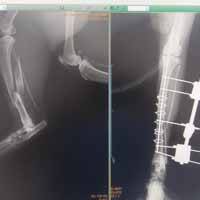

Yalıkavak veteriner kliniğimizde gerçekleştirdiğimiz ortopedik cerrahi uygulamalar:

Ortopedik cerrahi oldukça titizlik ve özen gerektiren cerrahi uygulamalardır. Diğer cerrahi disiplinlere nazaran asepsi ve antisepsi (sterilizasyon) konusunda ASLA hata kabul etmez. Eğer bu aşamada özensiz davranılırsa, postoperatif süreçte kemik dokunun iltihaplanmasına neden olup, kemiklerin kaynaması gecikmiş olur.